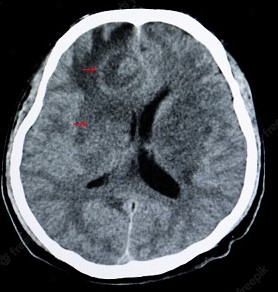

Cトキソプラズマ脳炎

臨床症状としては意識障害、けいれん、視力障害などがあげられる。

A脳炎の場合

頭部造影CTやMRIで、病変はリング状に造影される腫瘤として認められます。

トキソプラズマ脳炎の診断は、PCRによる髄液からの原虫遺伝子の検出によりますが、感度が低く、陰性であっても

感染は否定されません。